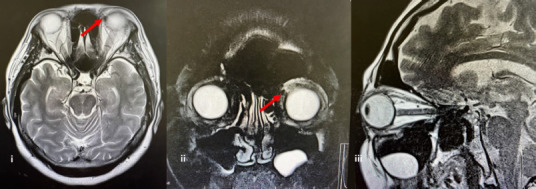

Proptosis, commonly referred to as 'bulging eyes', is characterised by abnormal protrusion of the eyeball. This condition can arise from a variety of underlying causes, including thyroid eye disease, orbital tumours, inflammatory disorders and vascular anomalies. Timely recognition of proptosis and the underlying cause is crucial due to potentially vision-threatening conditions. We present a case series of patients who presented with proptosis and proptosis-like condition in a primary care clinic. All cases exhibited bulging of the eyes with protrusion beyond 21 mm from the orbital rim. The first case involved proptosis due to cavernous haemangioma; the second was a case of pseudoproptosis; and the final case was Oue so underlying thyroid eye disease. A comprehensive evaluation, including detailed historn-taVing and radiological imaging, was essential in identifying the specific causes of proptosis for each case, thus allowing for appropriate management strategies to be implemented.